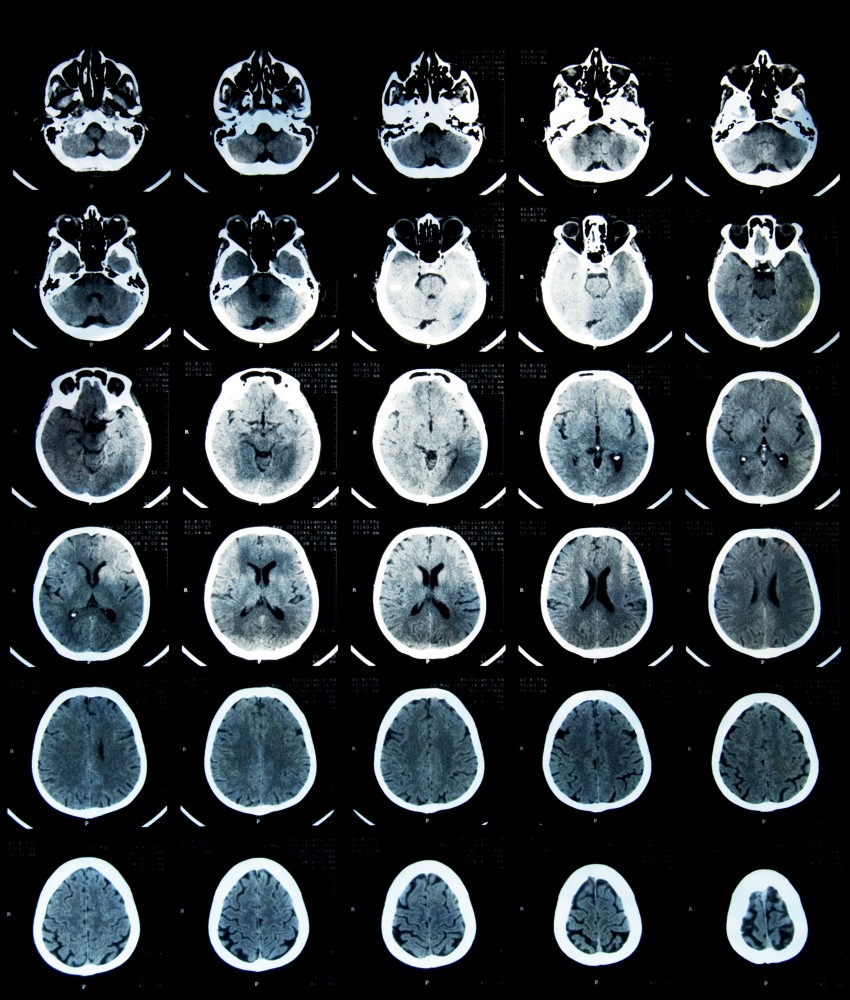

Comotie cerebrala la batrani. Aflati cum se manifesta o comotie care sunt masurile de prim ajutor si tratamentele impuse in aceasta situatie critica. Comotia cerebrala reprezinta de fapt un traumatism la nivelul creierului care apare in urma unei lovituri fiind insotita de modificari in functionarea acestuia insa fara a fi prezente deteriorari structurale in cadrul procedeelor imagistice nu se evidentiaza nicio modificare. Riscul este si mai mare in cazul in care trauma are loc la sfarsit de saptamana au descoperit cercetatorii fara a putea explica acest fenomen se arata in raportul publicat de journal de l association medicale canadienne cmaj citat de agentia france. în mod normal creierul este perfect echilibrat în craniu suspendat în lichidul cefalorahidian care îl protejează.

Leziunile traumatice minore sunt acompaniate de pierderea de scurta durata a functiei creierului din cauza. Evolutia comotiei este in general favorabila simptomele regresand treptat. Acum 10 zile mam lovit la cap cu un capac destuld e greu care atrecut razant pe crestetul capului dar am simtit putin lovitura pe moment nu am avut durere sau ameteala am fost la consult iar doctorita mia spus ca am avut noroc ca nu ma lovit capacul direct in cap mi a verificar reflexele nu am durae nimic capul de la. La aproximativ 4 din pacientii care au avut o comotie cerebrala se va observa la examenul ct o hemoragie intracraniana subdurala epidurala sau parenchimatoasa.